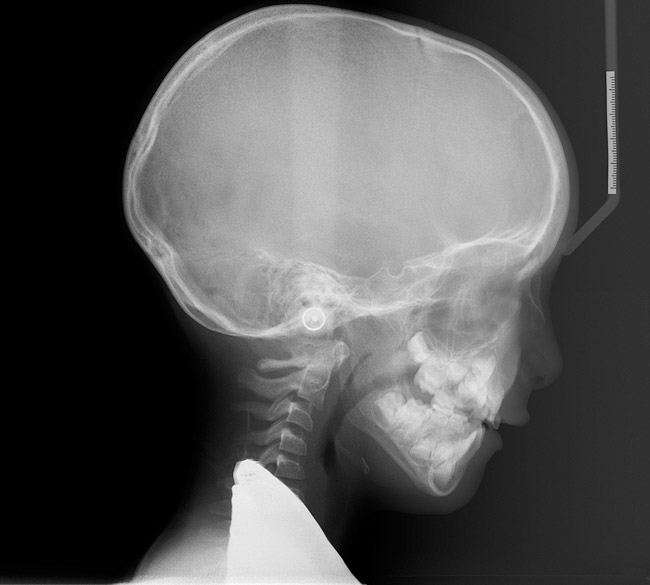

(3.) Three-year-old with a history of snoring, bruxing, and thumbsucking. Her father and brother were both diagnosed with OSA.

Figure 3

(4.) Patient presents bilateral crossbite and significant attrition. Father assists in retraction.

Figure 4